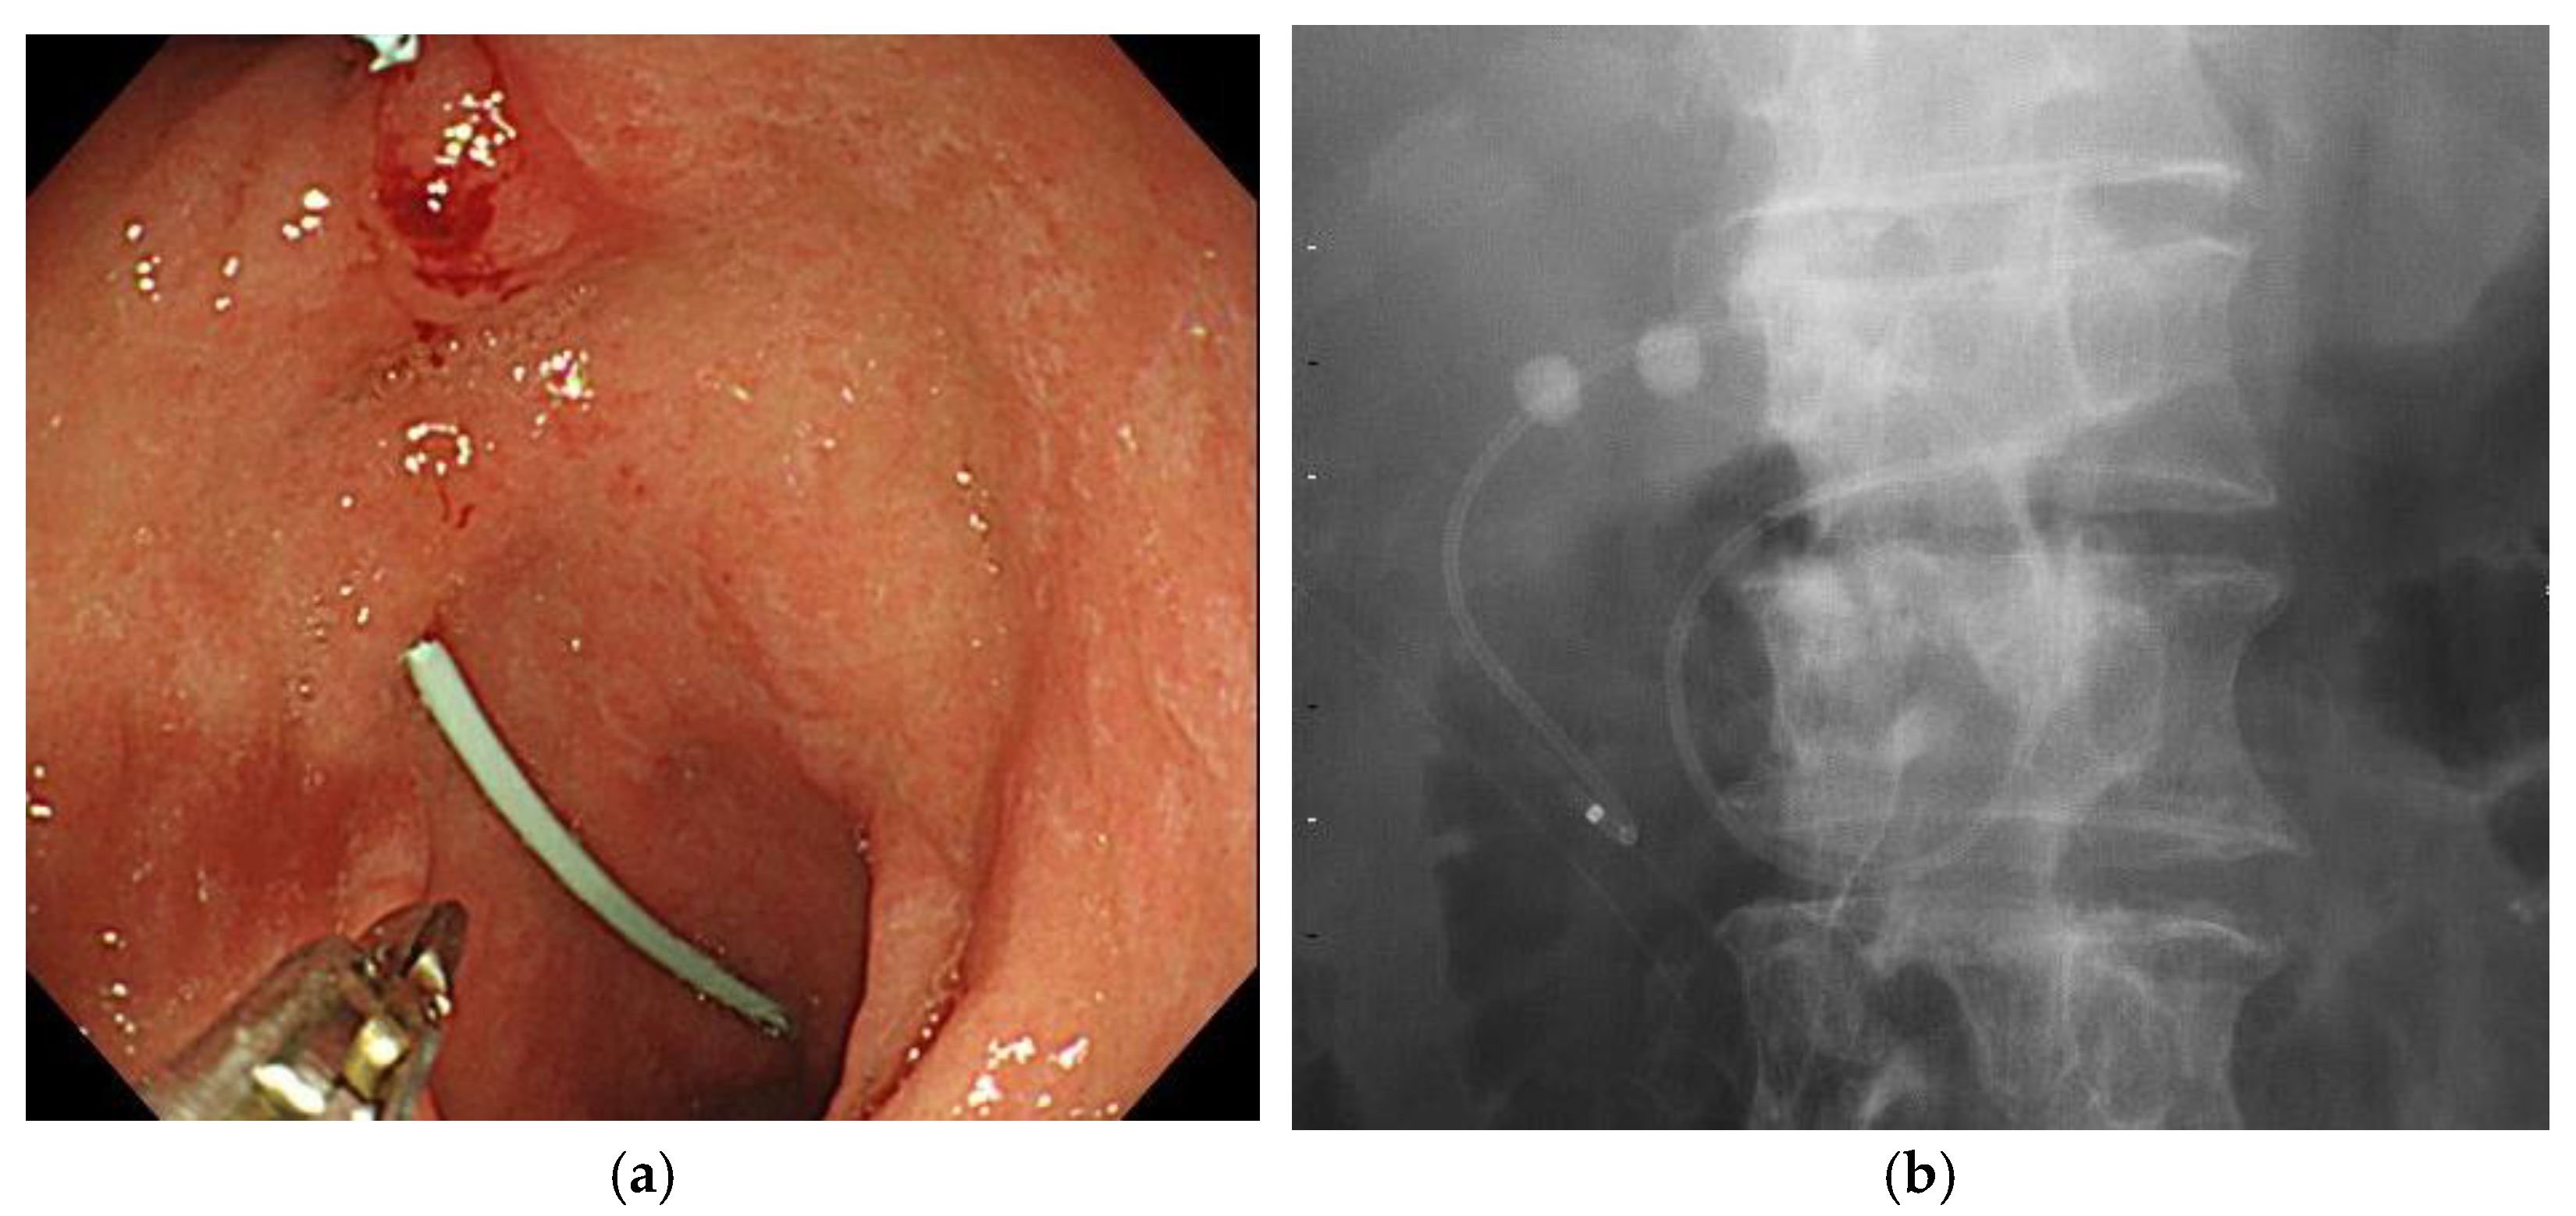

Figure 2.

EGBS after internalization by cutting the ENGBD tube. (a): Endoscopic image. (b): Fluoroscopy image. EGBS, endoscopic gallbladder stenting; ENGBD, endoscopic nasogallbladder drainage.